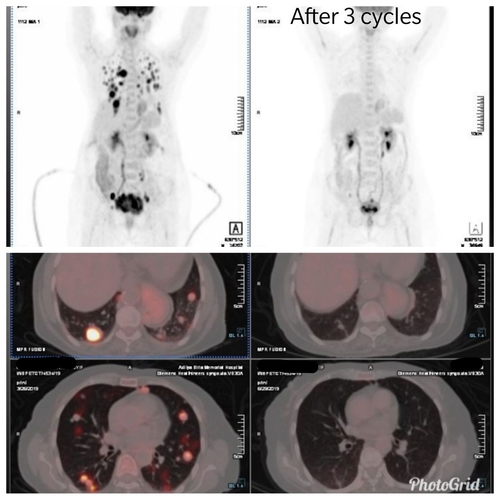

Is there any benefit of treating Stage 4 advanced cancers??This is a common question which many people ask us when we disclose the diagnosis of stage 4 cancer to relatives. In most cases, stage 4 widespread cancers are treated with non-curative ( palliative ) intent. However if properly treated, even such patients can have amazing long-standing responses and good quality of life.This 68-year-old lady presented with renal failure with a creatinine of 18 mg/dl and on evaluation was diagnosed to have cervical cancer with obstructive uropathy and multiple florid lung metastases. After initial stabilization and relieving the obstruction with DJ stenting, the patient was treated with chemotherapy. PET CT scan after 3 months of Chemotherapy showed a significant reduction of lung metastasis and cervical cancer mass. Patients creatinine became normal and she is able to carry out all her routine activities. After maximum response with chemotherapy, for the last 8 months, the patient is being maintained on simple oral chemotherapy drugs ensuring priority on disease control as well as the quality of life.